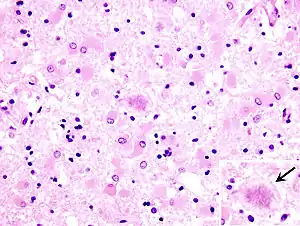

![]() Гістопалогогічні зміни у померлого від хвороби Кройцфельда-Якоба локалізуються у лобній частині головного мозку. Відмічена стрілкою гліальна вакуоля, всередині якої помітна велика витіювата бляшка. Забарвлення гематоксилін-еозином, збільшення у 40 разів Гістопалогогічні зміни у померлого від хвороби Кройцфельда-Якоба локалізуються у лобній частині головного мозку. Відмічена стрілкою гліальна вакуоля, всередині якої помітна велика витіювата бляшка. Забарвлення гематоксилін-еозином, збільшення у 40 разів | |